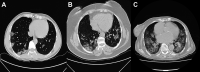

Patient and methods: The study was conducted with medical records of 987 (82%) patients with confirmed COVID-19 virus via real-time reverse transcription-polymerase chain reaction between March 11, 2020, and April 21, 2020. Patients were divided into 2 groups as computed tomography (CT)-negative and CT-positive groups considering the presence of the CT findings depicting COVID-19 disease.

Results: The mean age was significantly higher in CT-positive group than CT-negative group (41.53 ± 12.82 vs 36.61 ± 11.81, P < .001). Cough and shortness of the breath were observed with a significantly higher rate in CT-positive group than that of CT-negative group (44% vs 29.9%, P = .001 and 18.4% vs 9.7%, P = .002, respectively).